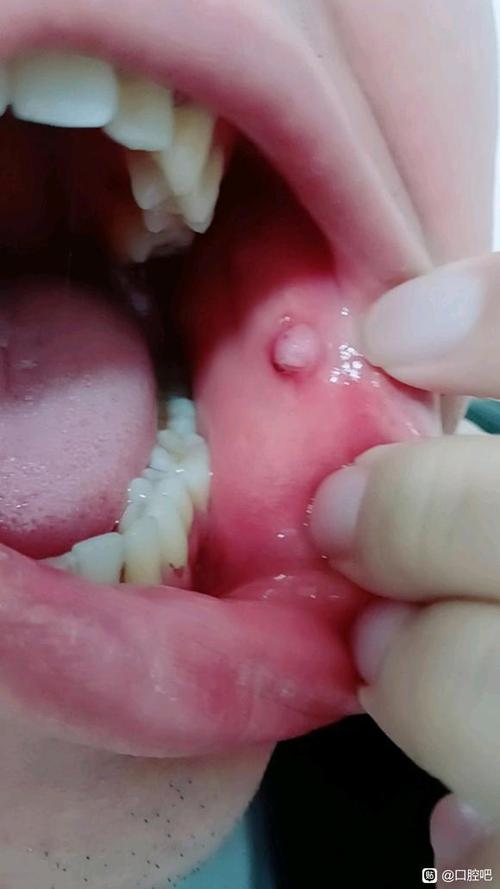

口腔内壁小肉疙瘩肿痛是何原因? 可能的原因分析 口腔内壁的小肉疙瘩和肿痛,通常由以下几种情况引起:(图片来源网络,侵删) 口腔溃疡 (最常见) 特点:通常是圆形或椭圆形的溃疡面,中间凹陷,周围有一圈红晕,表面覆盖着黄色或白色的假膜。疼痛感非常明显,尤其是在进食、说话或刷牙时,虽然溃疡本身是“凹”的,但其周围的组织可能会因为炎症反应...